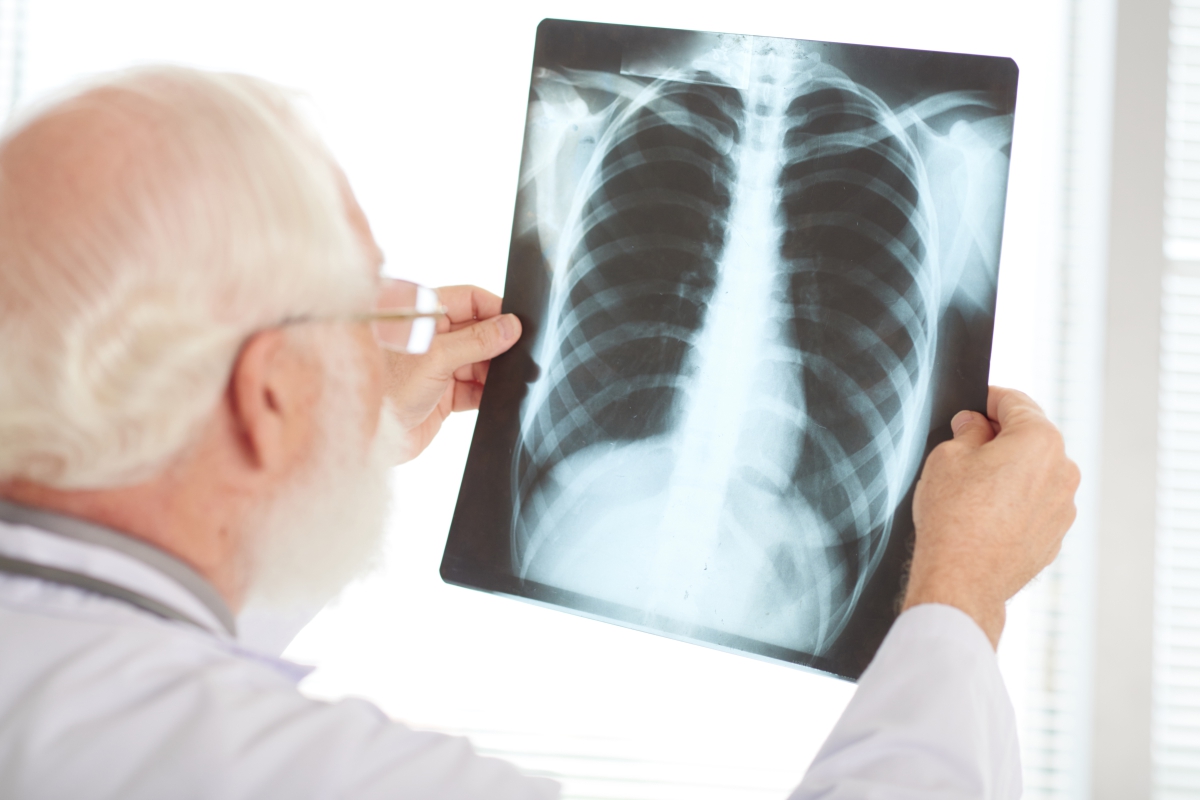

The truth is that your lungs, just like your heart, joints, and other parts of your body, age with time. They can become less flexible and lose their strength, which can make it more difficult to breathe. But by adopting certain healthy habits, you can better maintain...